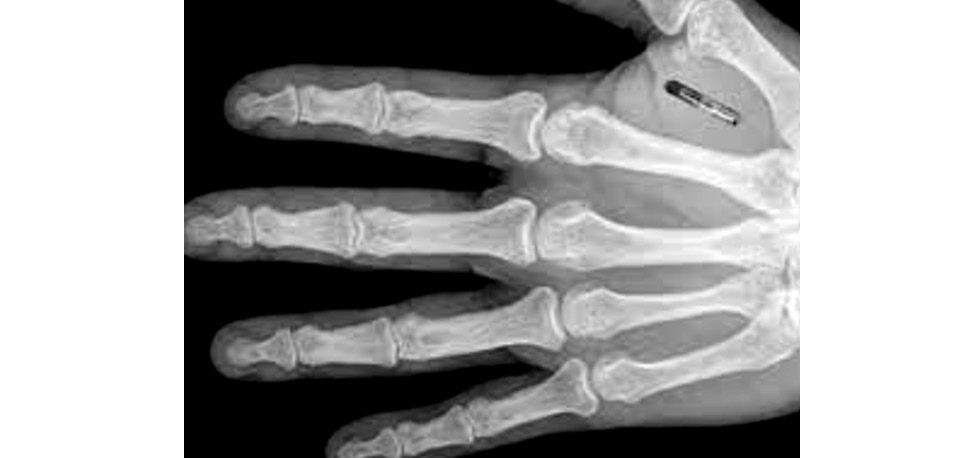

Следует отметить, что чипирование сотрудников правоохранительных органов ― идея не новая и уже имела место на практике. В 2004 году 160 сотрудников прокуратуры Мексики, включая Генерального прокурора М. Де ла Конча, прошли процедуру имплантации микрочипов с целью повышения конфиденциальности и безопасности. Эта процедура позволила чипированым сотрудникам получить уникальный идентификационный номер, который через радиочастотную идентификацию RFID предоставлял им доступ к новому федеральному информационному центру по борьбе с преступностью и другим сведениям ограниченного характера. Кроме того, внедрение чипов позволяло использовать их для поиска и обнаружения пропавших сотрудников. Чипирование также планировалось в мексиканской армии и полиции2. Несмотря на отсутствие более подробной информации, в том числе о результатах, эффективности и минусах данного опыта, его применении либо внедрении в других государствах, в целом можно свидетельствовать, что чипирование сотрудников правоохранительных органов имеет не только теоретический, но и практических характер. Вместе с тем мексиканский опыт позволяет выделить два преимущества чипирования ― личную безопасность сотрудников и их доступ к базам данных (рис. 1–3). Правоохранительная служба предполагает повышенные риски для жизни и здоровья сотрудников, в том числе при задержании правонарушителей и преступников, освобождении заложников, пресечении массовых беспорядков, конвоировании, охране и побегах заключённых, охране общественного порядка, осуществлении оперативно-розыскных мероприятий и выполнении других служебных обязанностей. Не исключается также нападение на сотрудников правоохранительных органов и членов их семей.

Рис. 2. Рентген руки с чипом.

Fig. 2. X-ray of a hand with a chip.